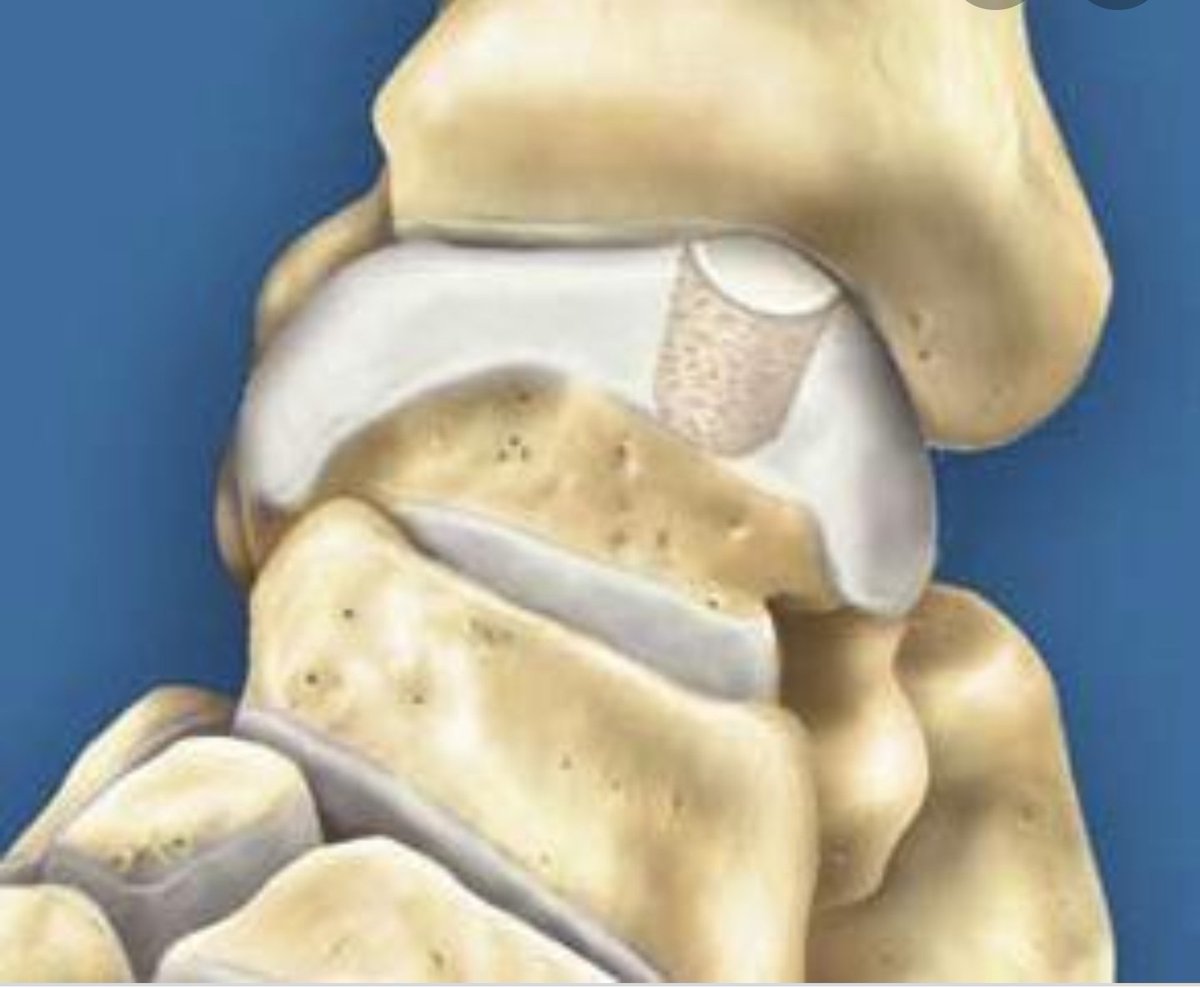

او ما يسمى الآفة الغضروفية osteochondral

defect

٢-زراعة غضروف في الكاحل: للإصابة اللتي اكثر من ١سم مربع